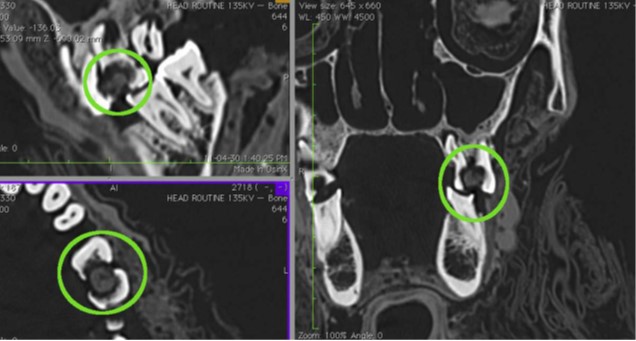

La presenza di piccoli fori sull’osso mascellare o mandibolare di alcune mummie ha fatto pensare a trapanature per drenare il pus dagli ascessi dentali. A parte l’estrema dolorosità di tale operazione, gli studiosi dibattono se siano effettivamente i segni di antiche trapanature o perdite naturali di materiale osseo